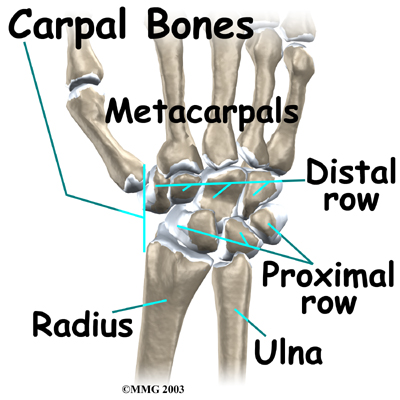

There are 15 bones that form connections from the end of the forearm to the hand. The wrist itself contains eight small bones, called:

These bones are grouped in two rows across the wrist. The

is where the wrist creases when you bend it. Beginning with the thumb-side of the wrist, the proximal row of carpal bones is made up of the scaphoid, lunate, and triquetrum. The second row of carpal bones, called the:

meets the proximal row a little further toward the fingers. The distal row is made up of the trapezium, trapezoid, capitate, hamate, and pisiform bones.

The proximal row of carpal bones connects the two bones of the forearm, the radius and the ulna, to the bones of the hand. The bones of the hand are called the

metacarpal bones. These are the long bones that lie within the palm of the hand. The metacarpals attach to the phalanges, which are the bones in the fingers and thumb.

One reason that the wrist is so complicated is because every small carpal bone forms a joint with the bone next to it. This means that what we call the wrist joint is actually made up of many small joints.